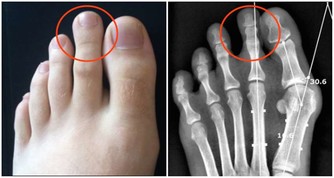

4、排便費力,排出的大便有壓跡,呈槽溝狀、扁條狀、細條狀等,一定要做直腸指診。